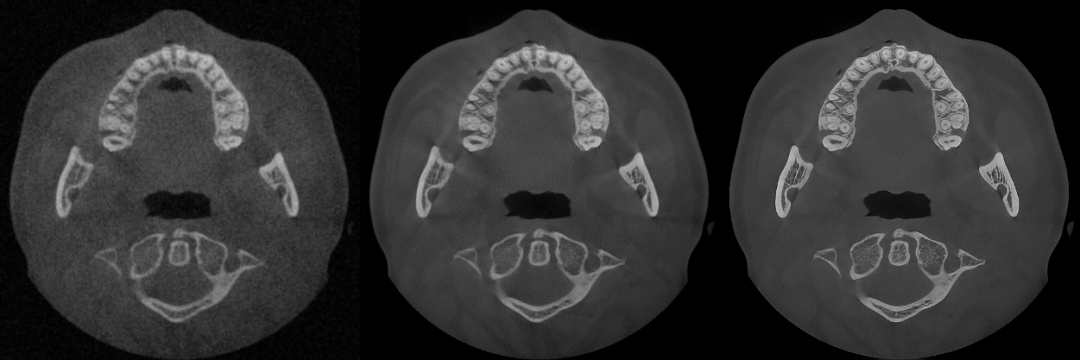

▲From left to right: Original Image, Mainstream Algorithm, "PD" Technology